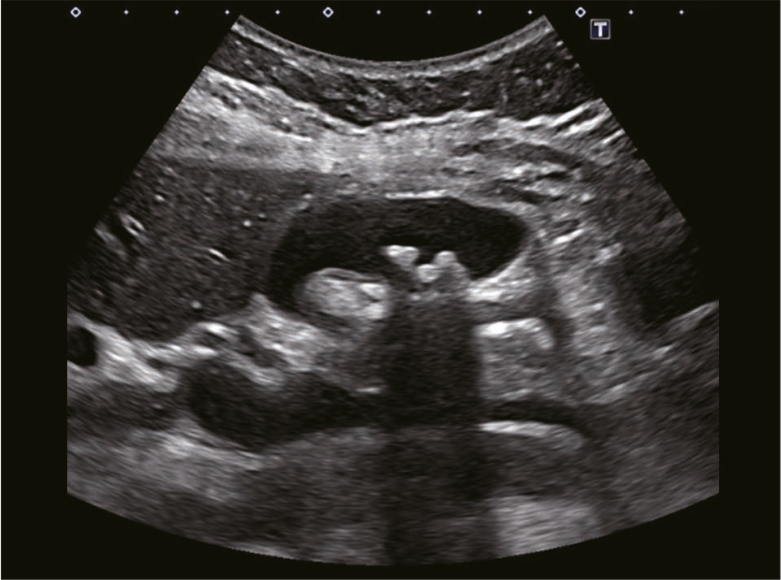

• 右季肋部痛を主訴とする胆嚢結石症例に対しLap-Cを予定した(図1)。DIC-CTでは、肝後区域胆管枝から胆嚢管が分岐する胆道破格を認めた(図2)。術中に肝後区域胆管を誤認・損傷するリスクを考慮し、ICG蛍光胆道画像を併用した手術方針とした。

• 図1

図2